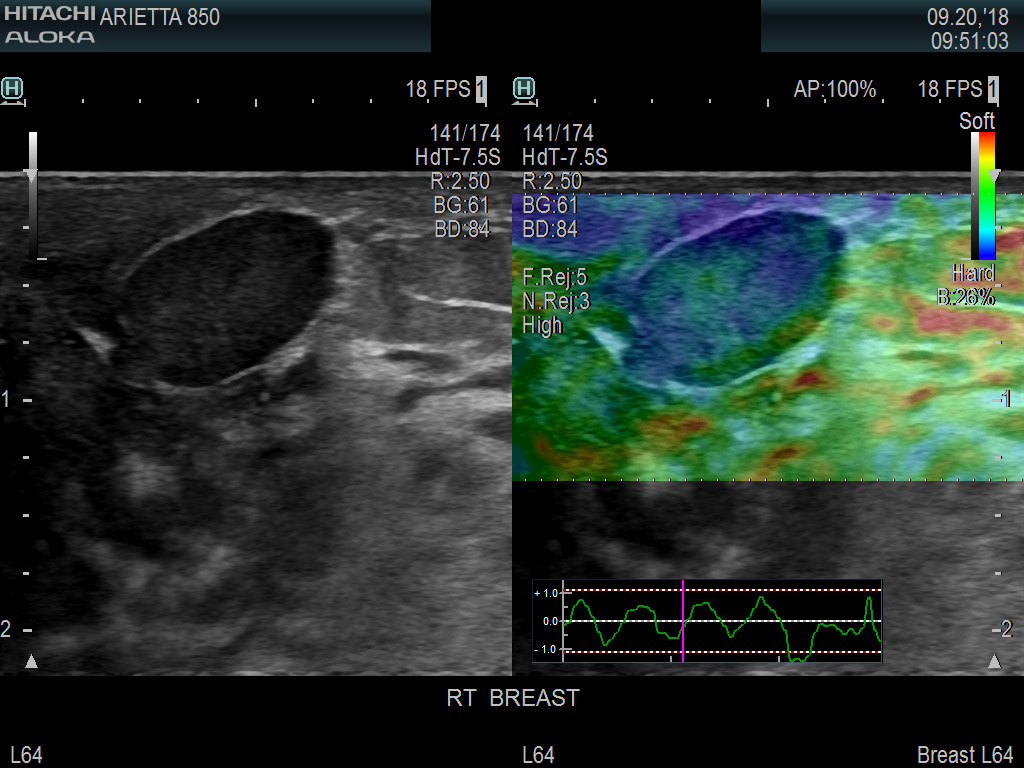

Superior guidance for all applications

Fujifilm Healthcare's dedication to Surgeons provides outstanding ultrasound technology, professional support and the specialized tools necessary to best perform comprehensive real-time ultrasound imaging in Breast Surgery, General Surgery, Laparoscopic Surgery, Neurosurgery, Robotic Surgery and Surgical Oncology.

Fujifilm Healthcare’s ARIETTA Precision features state-of-the-art digital architecture and advanced imaging technologies to redefine the capabilities of surgical ultrasound.

Imaging Clearly Defined

State-of-the-art digital architecture and advanced imaging features to redefine the capabilities of surgical ultrasound.